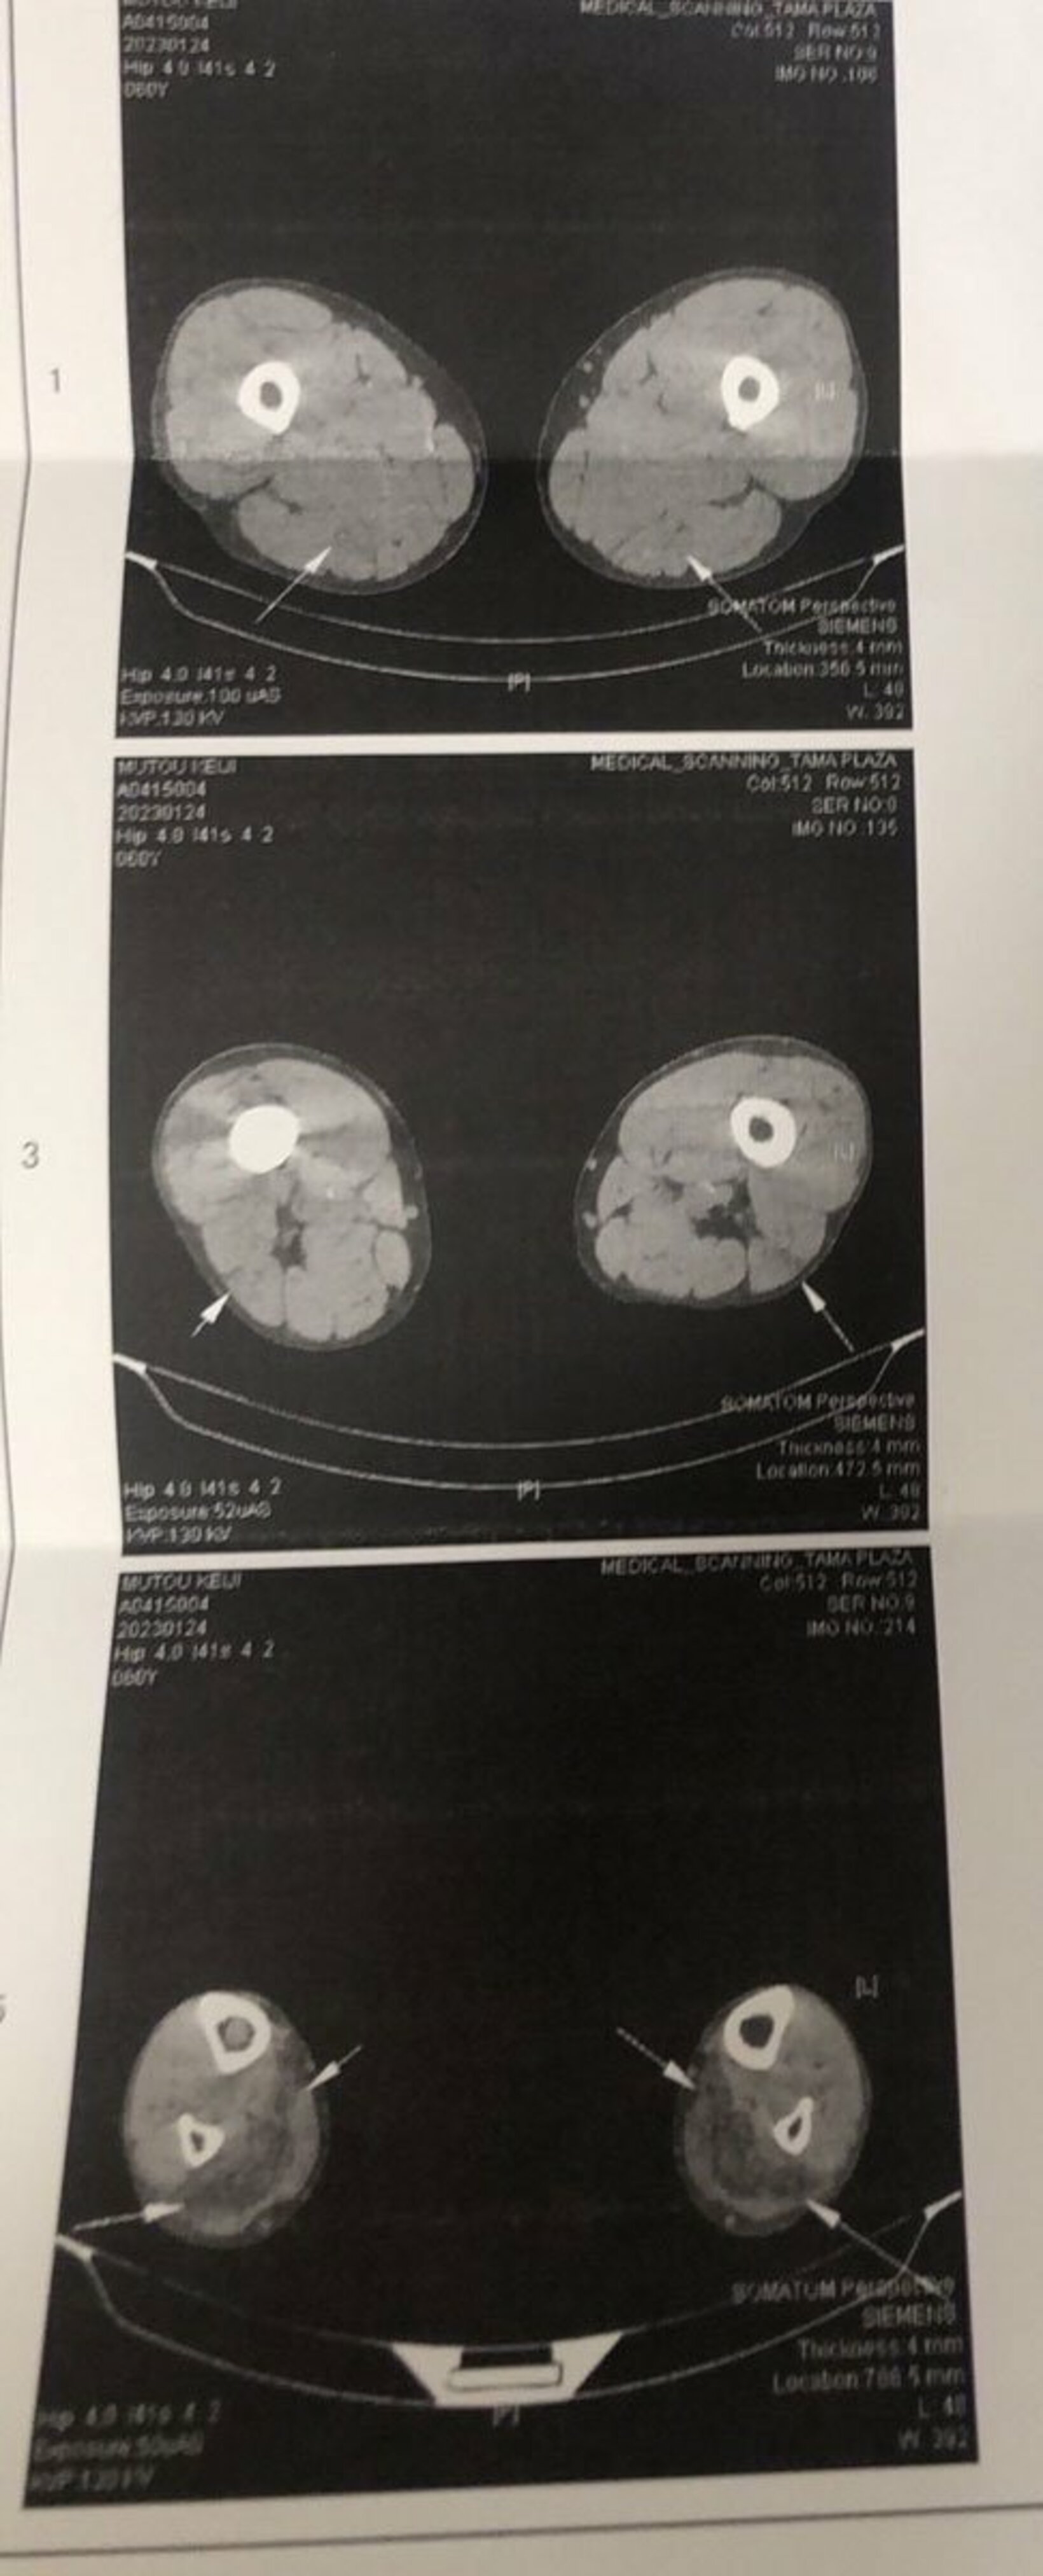

武藤の肉離れのCT画像